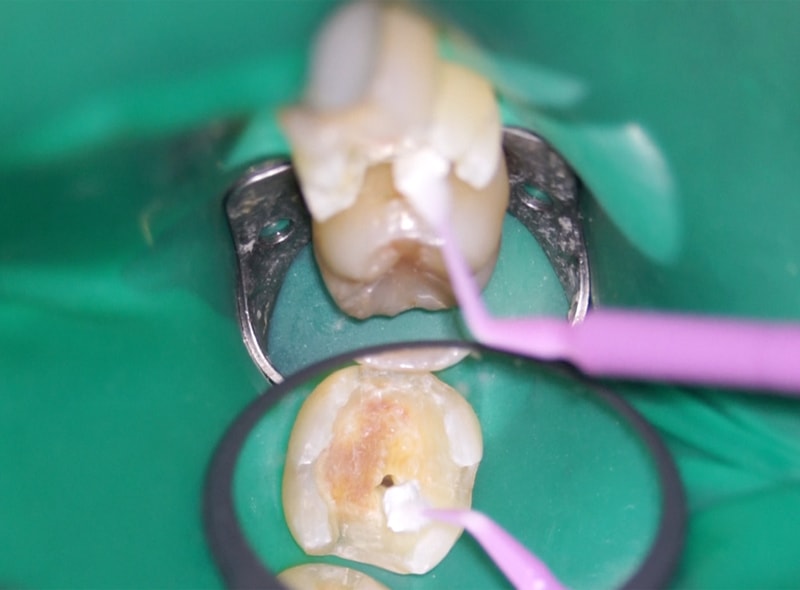

ラバーダムの使用

治療中の唾液や細菌が歯に触れないよう、ラバーダム(ゴムのシート)を使用しています。

これにより、健全な歯質への感染を防ぎ、治療の精度と安全性を高めることができます。

精密な処置を行ううえで欠かせない大切な工程です。

歯髄温存療法(MTA療法)

虫歯が深くまで進行し、神経に達してしまった場合でも、感染していない部分を残すことを目指す治療法です。

以前は神経が露出すると抜髄(神経を抜く処置)が一般的でした。

そこで登場したのがMTAセメントを用いた温存療法です。

MTAセメントは強いアルカリ性で細菌を殺す作用があり、固まる際にわずかに膨張して隙間なく封鎖します。